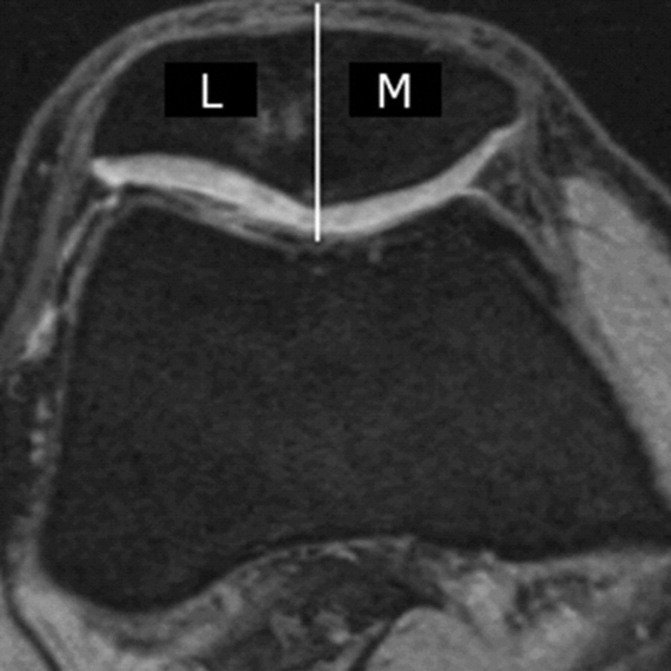

Subregional joint division using MRI Osteoarthritis Knee Score (MOAKS)

• cartilage morphology and subchondral bone marrow lesions (BMLs) in ​​14 subregions